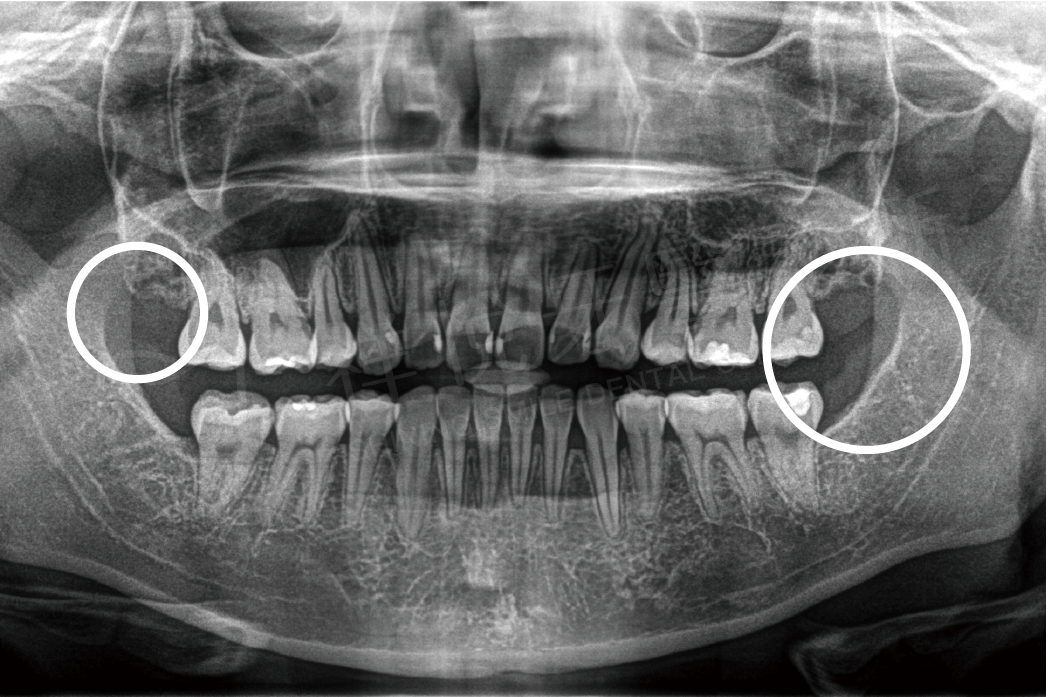

阻生齒拔除

拔牙前 拔牙後

拔牙前

拔牙後